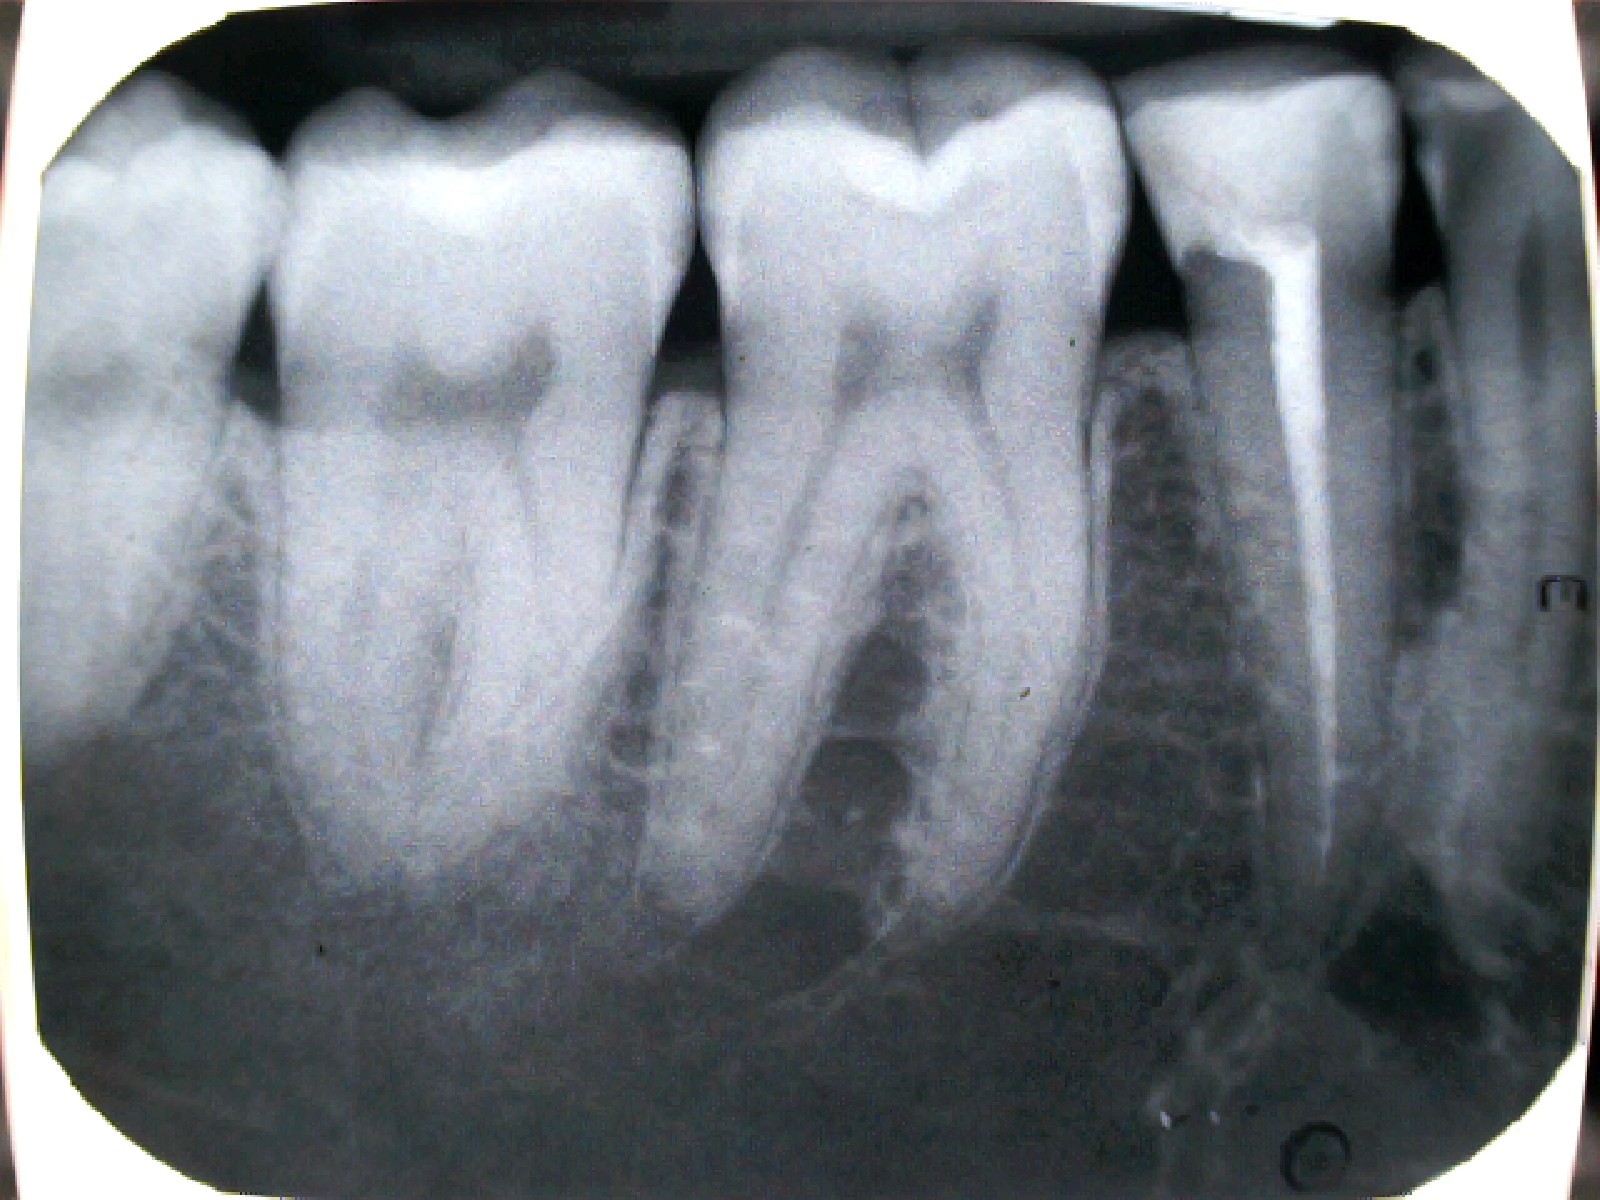

Álút képződés

Perforáció (fenti kép)

Túltömés

Alultömés

Lépcsőképződés

Tű-törése (fent)

Feltáratlan gyökércsatorna (fent)

Rosszul záró/nagy kiterjedésű tömés

Anatómiai okok a sikertelenség esetén:

Elmeszesedett csatorna

Kialakult endo-parodontális lézió